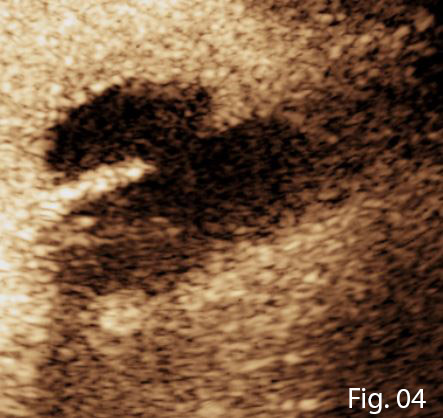

B-mode ultrasound demonstrated complicated gallstones with low level echogenic debris within the gallbladder. The gallbladder wall was thickened and ill-defined anteriorly (Figure 1). Within segment V of the liver, adjacent the anterior gallbladder wall was an ill-defined hypoechoic lesion containing complex fluid components, these findings were suggestive of a hepatic abscess. A second larger hepatic abscess was noted in segments V/VIII (Figure 2).